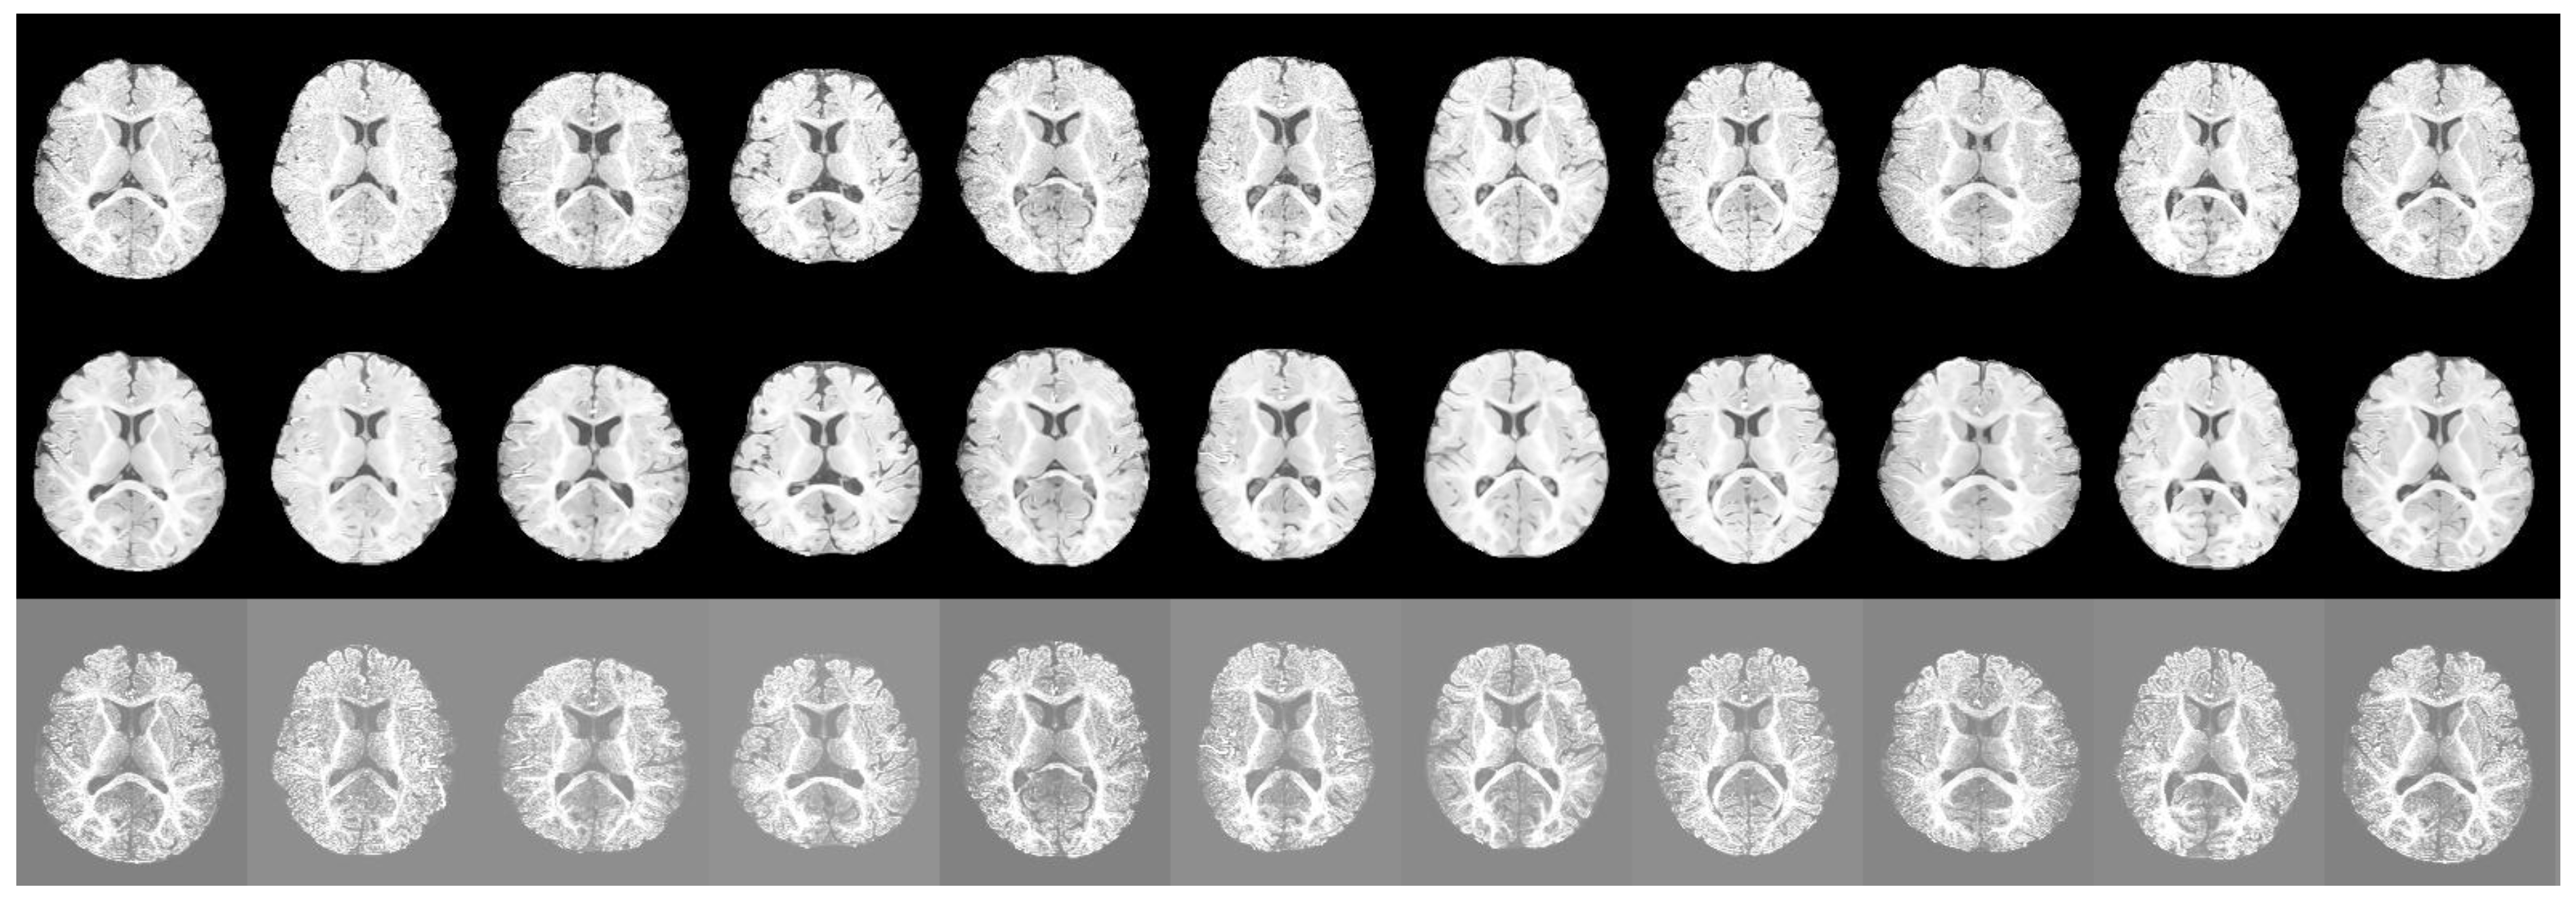

5.1. Segmentation Results